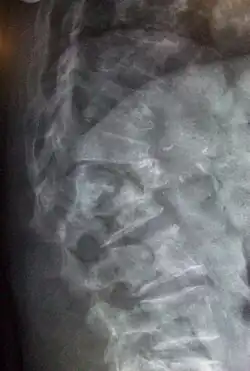

Conventional radiography

Conventional radiography is useful, both by itself and in conjunction with CT or MRI, for detecting complications of osteopenia (reduced bone mass; pre-osteoporosis), such as fractures; for differential diagnosis of osteopenia; or follow-up examinations in specific clinical settings, such as soft tissue calcifications, secondary hyperparathyroidism, or osteomalacia in renal osteodystrophy. However, radiography is relatively insensitive to the detection of early disease and requires a substantial amount of bone loss (about 30%) to be apparent on X-ray images.[115][116]

The main radiographic features of generalized osteoporosis are cortical thinning and increased radiolucency. Frequent complications of osteoporosis are vertebral fractures, for which spinal radiography can help considerably in diagnosis and follow-up. Vertebral height measurements can be objectively made using plain-film X-rays by using several methods, such as height loss together with area reduction, particularly when looking at vertical deformity in T4-L4, or by determining a spinal fracture index that takes into account the number of vertebrae involved. Involvement of multiple vertebral bodies leads to kyphosis of the thoracic spine, leading to what is known as dowager's hump.[117][118]